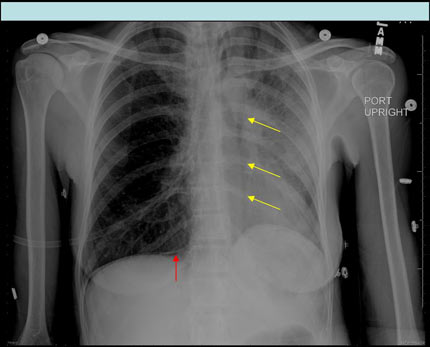

Radiografía frontal vertical del tórax demuestra aire debajo de la hemidiafragma derecha (flecha roja) y aire moviéndose a lo largo del corazón izquierdo y el borde mediastínico hacia el vértice (flechas amarillas) consistente con un neumoperitoneo (rojo) y neumomediastino (amarrillo).